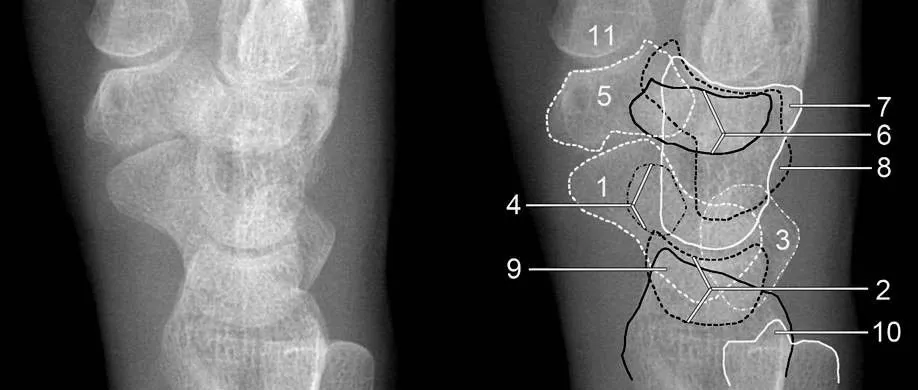

腕关节是一个复杂的结构,由8块腕骨组成。在阅片时,我们首先要注意腕骨的排列是否正常。正常情况下,腕骨应该排列成两条平行的弧线。如果发现弧线中断或不连续,就要高度怀疑可能存在脱位或骨折。

以月骨脱位为例,这是最常见的腕骨脱位类型之一。在正位片上,我们可能会看到月骨旋转并与头骨重叠,头月关节和桡月关节间隙消失。而在侧位片上,月骨向掌侧脱位是其特征性表现。值得注意的是,舟状骨、头骨与桡骨的关系通常保持不变。

另一个常见的类型是月骨周围脱位。这种情况下,正位片上可能会显示头月骨重叠,关节间隙消失或变窄。侧位片上,月骨原位不动,但桡月关节正常,月骨上关节面空虚。头状骨通常位于月骨背侧缘的后上方,舟状骨向背侧脱位。

在阅片时,我们还需要注意一些细节。例如, 腕关节间隙应该小于等于2mm ,仅桡腕关节间隙稍宽。如果发现关节间隙异常增宽或狭窄,就要警惕可能存在脱位。此外,腕骨的形状和轴向也是重要的参考指标。例如, 月骨呈梯形,近侧边缘平行于远侧边缘。 如果月骨倾斜,可能会呈现三角形,这可能是脱位的表现。